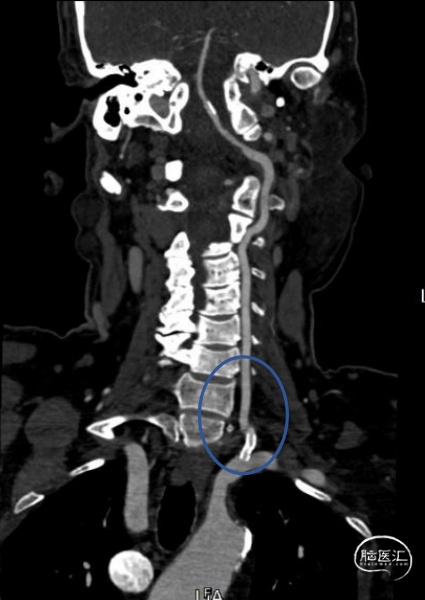

➢头颈部CTA(三维重建MIP像)

➢头颈部CTA(原始像)

患者于入院前10天突发视物重影,5分钟左右缓解,当晚18:00出现颈后不适伴左上肢持续性麻木,10天后来我院急诊神经内科就诊,就诊时测血压191/93mmHg,自行服用拜新同1粒。 完善头颅MRI:桥脑、两侧小脑急性缺血性梗塞;右侧基底节软化灶;两侧侧脑室旁少量白质疏松;老年脑改变。 入院后予药物保守并完善头颈部CTA:左侧颈内动脉虹吸段多发钙化斑块、混合斑块,管腔轻-中度狭窄,C7段小动脉瘤。右侧颈内动脉虹吸段多发钙化斑块,管腔轻度狭窄。右侧椎动脉纤细,V4段局部显示欠清。左椎V1、V2段非钙化斑块,局部管腔重度狭窄-闭塞,V4段钙化斑块,管腔中度狭窄。右侧部分型大脑后动脉,P1段重度狭窄,P2段中度狭窄。双侧大脑中动脉M2段中至重度狭窄。 告知患者病情存在进一步进展可能,患者家属商量后要求手术治疗。

术前影像考虑右侧孤立椎,左侧椎动脉V1段重度狭窄、狭窄段以远扭曲成襻且合并长节段多发动脉粥样硬化狭窄改变(夹层待排),同时左椎V4段局部重度狭窄可能;